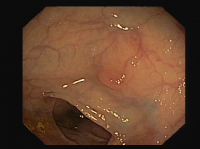

Refer to caption

Figure 2: Example of a colonoscopy image and its corresponding ground truth: (a) Original image, (b) Polyp mask, (c) Specular highlights mask and (d) lumen mask.